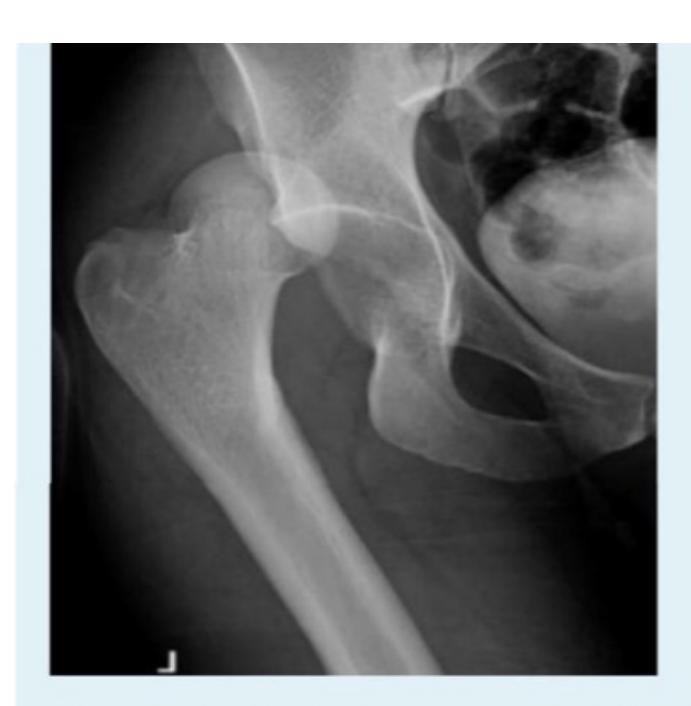

A 70-year-old inactive female presents to the emergency department after falling down in the bathroom. Sheโs been complaining from hip pain and inability to bear weight. Which of the following is the most appropriate choice of treatment?

- C. Bipolar hemiarthroplasty

Intertrochanteric Fracture

Diagnosis: Intertrochanteric fracture of neck of femur Treatment: Dynamic hip screw or proximal femoral nail

A 50-year-old male tripped over the edge of carpet at home. He heard a crack and is unable to walk. He gave history of progressive weight loss. On clinical examination, he was in pain with a deformity at upper right thigh. He looks pale.

What are the key x-ray findings?

- Decreased bone density in the right proximal femur

- Fracture in the neck of the femur

- AP view of the right proximal femur

What is the diagnosis?

- Pathological fracture due to osteoporosis